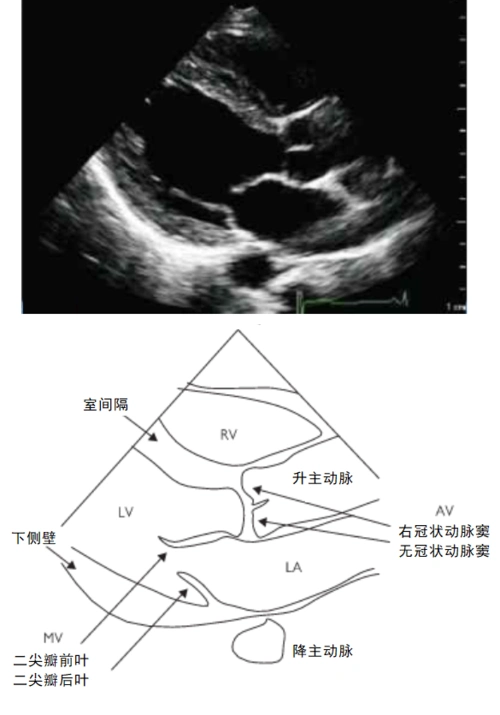

哪些心脏超声表现,几乎没有临床意义?

经典心脏超声切面图及解剖解释

零基础学心超一天一图一讲解002之右室流入道长轴切面